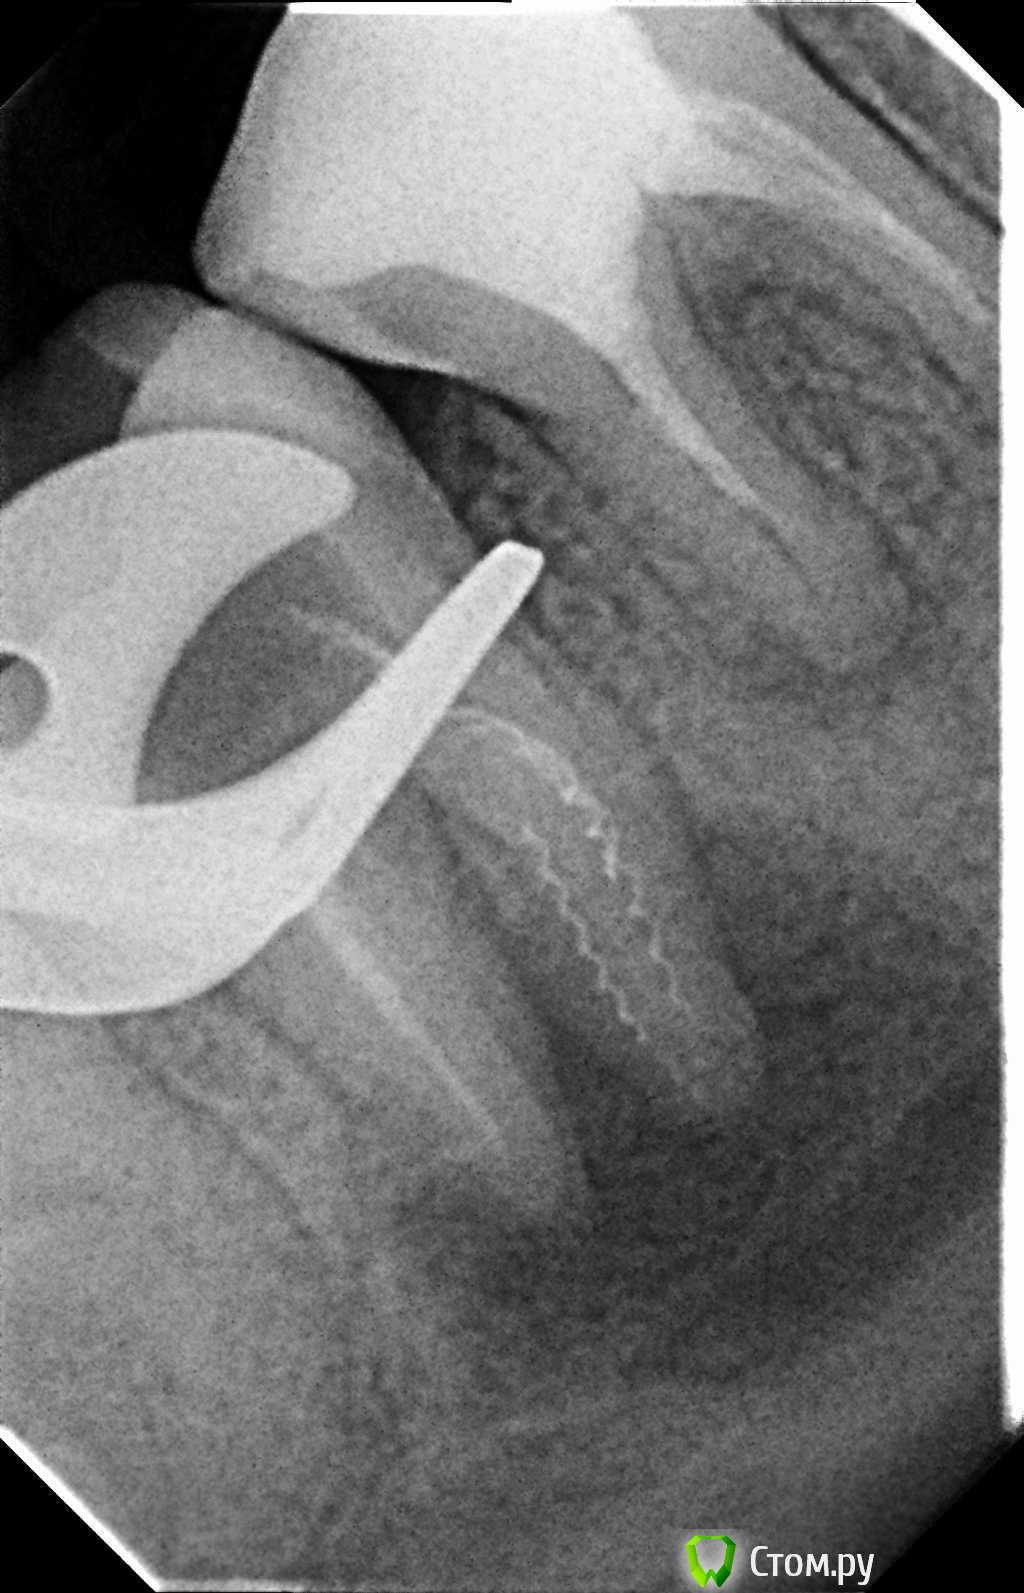

Л Ю С Я Опубликовано 10 января, 2014 Поделиться Опубликовано 10 января, 2014 .Новый кейс-совсем свежий пока без долгосрочного результата.Пациентка попала случайно удаляла зуб 28 и хирург сделал ОПТГ,где стали видны обширные периапикальные процессы в области 37 47.Побывав у меня на консультации и услышав план лечения и стоимость,пациентка решила видимо полечить подешевле.,побывав на консультациях в нескольких клиниках и в итоге даже попала к главному стоматологу нашей области. Все ей сказали что удаление онли. Вернулась,-засада была в том что план я писал исходя из ОТПГ не сделав прицел(виноват),сделав прицел понимаю что все сложнее чем я думал-ну что же тем интереснее.Переписав план лечения и подняв ценник на 40%(пациентке не оставалась выбора),начали лечение.1-посещение-ревизия пломбы.понимаю что кто то до меня с маниакальным упорством пытался запломбировать мезиальный язычный канал каналонаполнителями. Убрал два фрагмента из верхней трети мезиального язычного.2-посещение еще фрагмент из мез язычного плюс немного с дистальными поработал(их оказалось два сплит в верхней трети)3-визит обошел фрагмент в мезиальном щечном и доработал остальные каналы.4-визит -паковка.На предпоследнем снимке видны поры-допаковал(просто на финальном не очень видно)Класс! Ждем рекол через 6 месяцев. Паковка чем? Сквирт? Ссылка на комментарий